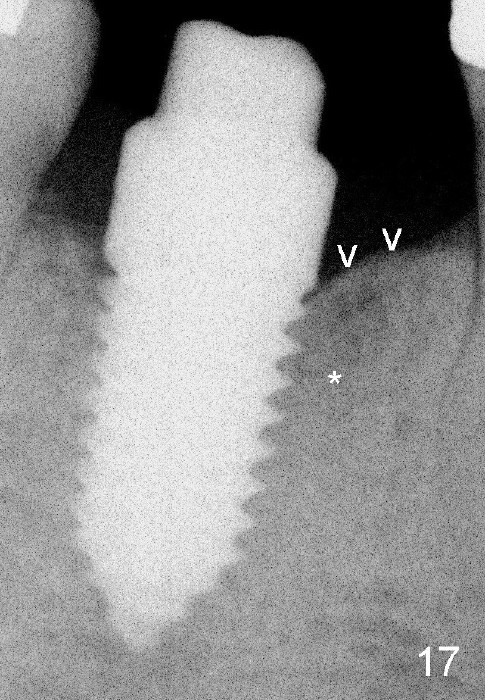

Fig.11: immediately post implantation (6x14 mm one piece). Fig.15: increased bone density in the mesial and distal sockets 3.5 months postop. Fig.17: the density of the mesial socket increases (*) with formation of the cortex (lamina dura (v)) coronally 8.5 months postop.